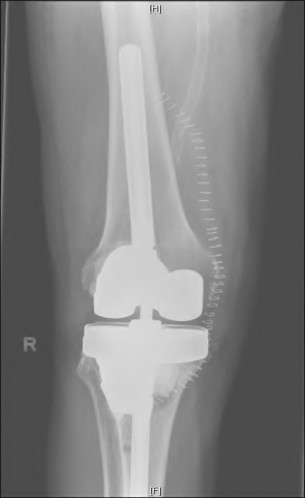

Question 18

During a revision total knee arthroplasty, removal of the tibial component reveals a massive contained metaphyseal defect measuring 3 cm deep, but with an intact cortical rim. According to the Anderson Orthopaedic Research Institute (AORI) classification, what type of defect is this, and what is the preferred method of management?

Explanation